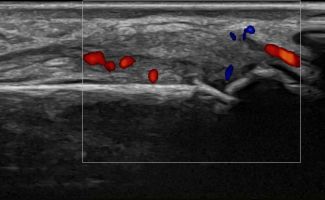

Rheumatic Diseases

- Rheumatoid Arthritis

- Psoriatic Arthritis

- Osteoarthritis